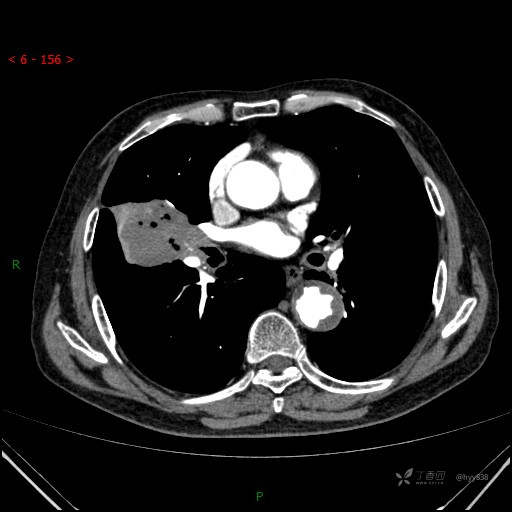

胸部CT肺窗

增强动脉期